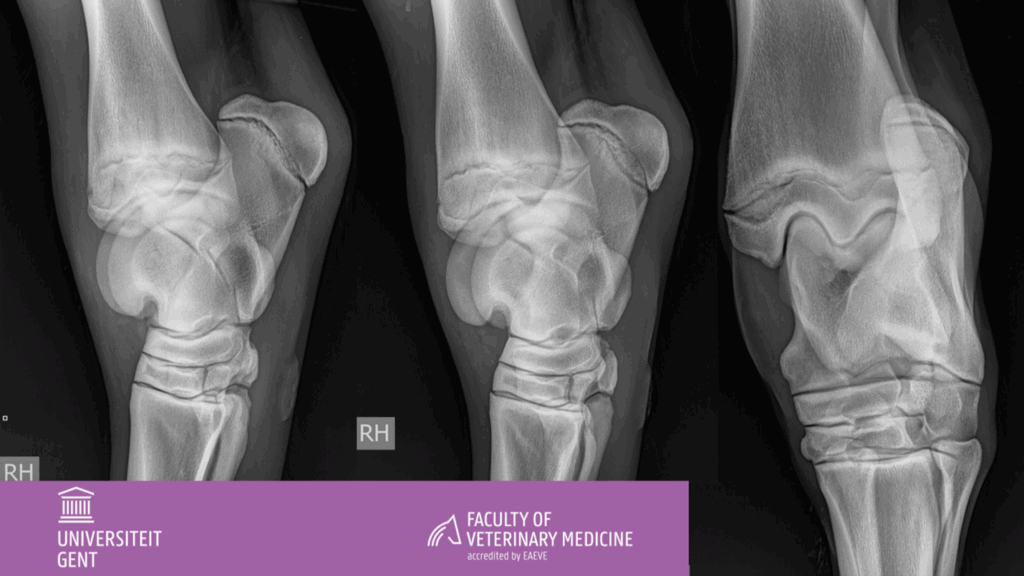

Atypische OCD

Anamnese 18 maand oud warmbloed paard.   Plots matige zwelling van de rechter sprong.   Klinisch onderzoek  Fluctuerende opzetting van het tarsocruraal gewricht.  Het paard is niet mank in stap of draf in...